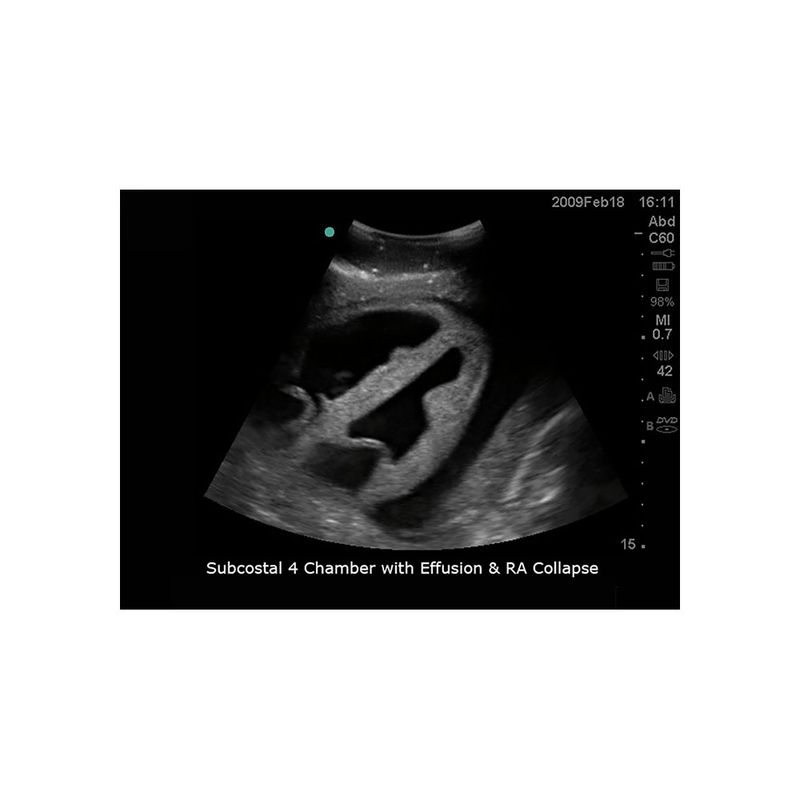

模型具有精准的内外部解剖结构,能与任何带经食道超声探头、心脏探头及腹部探头的超声影像检查设备联合使用,可进行经食道超声心动图(TEE)、经胸廓心超声心动图(TTE)、超声引导下心包穿刺术等完整操作流程训练。适合于心血管内科、急诊科、重症医学科、超声科等学科使用。